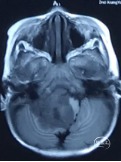

术后复查影像学资料

头部CT显示病变已切除,未见明显颅内血肿。头部MRI显示病变已切除未见肿瘤残留。

术后MRI